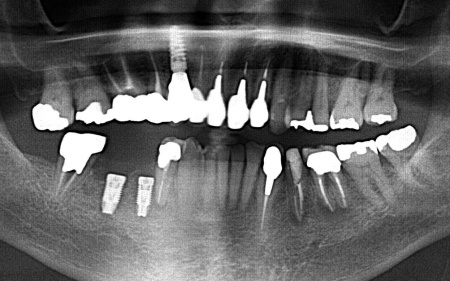

歯やあごの骨の状態を詳しく調べるためレントゲン検査を行った結果、右下の奥歯2本(第2小臼歯、第1大臼歯)は、歯根が縦方向に割れている可能性が高いと考えられました。

しかし、レントゲン画像だけでは歯根の状態を正確に判断することはできません。

次にCT検査を行い、骨の量や神経の位置を確認したうえでインプラント治療の計画を立てています。

完成した治療計画をもとに、インプラントをあごの骨に埋める手術を実施しました。